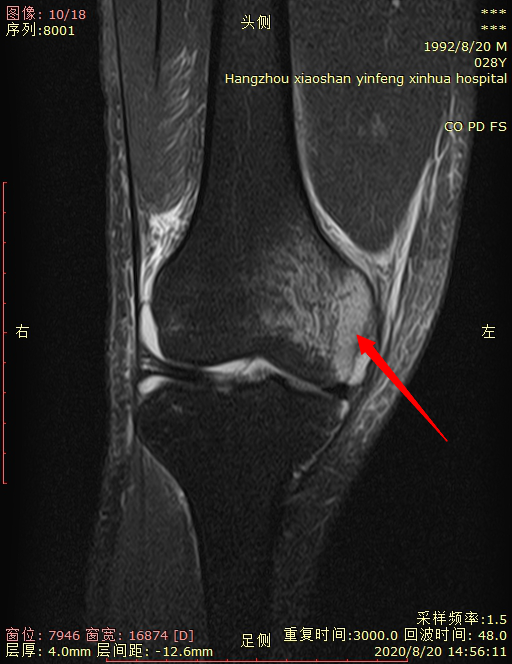

04 右膝关节骨挫伤。